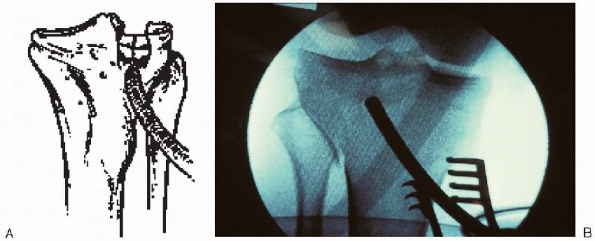

Although useful for simpler fractures, preoperative planning is

critical for more complex injuries. This forces the surgeon to

understand the “personality of the fracture” and mentally prepare an

operative plan. All aspects of the reduction and fixation should be

drawn out to help avoid technical pitfalls and ensure that all the

needed equipment is available.

![]() |

|

FIGURE 30-5. Preoperative plan for operative treatment of a lateral tibial plateau fracture.